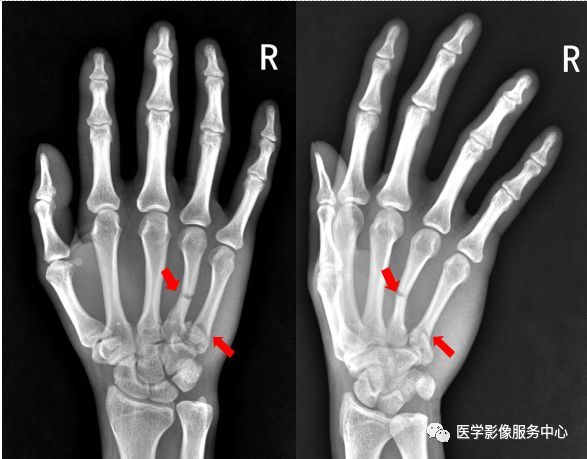

手指骨裂 Www Shianwang Com

右手大拇指末节骨折图片 第1页 图说健康

收藏 独立值班 这些骨折你都看出来了吗 附注解 移位